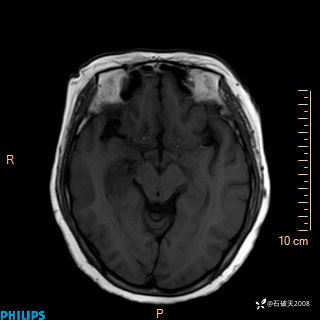

颅内占位,影像征象不是很丰富,有病理

hyy838 推荐女 62岁 主 诉:头晕12小时,加重1小时。

现病史:患者于12小时前无明显诱因出现头晕,呈持续性,无天旋地转及行走不稳,伴恶心、呕吐,呕吐共5次,呕吐物为胃内容物(具体性质不详),无胸闷、胸痛、心慌,无腹痛、腹泻,无咳嗽、咳痰,无发热、意识不清、肢体抽搐及大小便失禁等,1小时前患者上述症状加重,未诊疗,为求进一步治疗急自行来我院,门诊以“头晕待查”为诊断收入我科,发病来,神志清,精神差,饮食、睡眠差,大小便正常,体重未见明显下降。

DWI

ADC